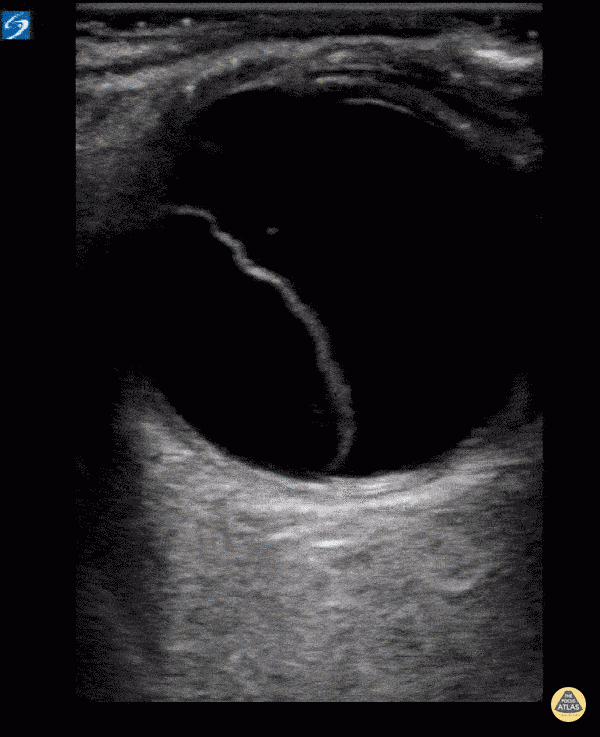

Orbital - Retinal Detachment

Retinal detachment in a patient with 1 day of a right sided visual field cut.Literature has shown sensitivity for this test to be 97-100% and specificity 83-100%. So next time ask yourself... is your fundoscopic exam that good? Dr. William Scheels